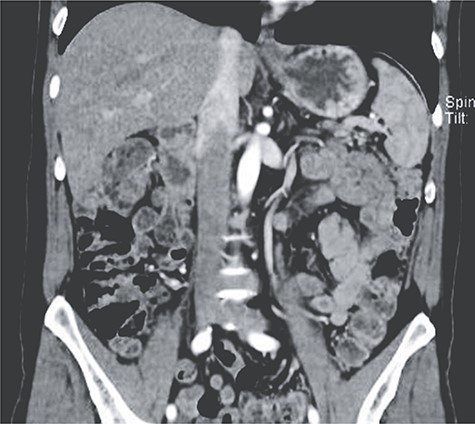

Patient is a 58-year-old male, with past medical history of pancreatogenic diabetes and cholecystectomy. He presented to the emergency room with a 2-day history of severe episodes of bright red blood stool, abdominal pain and difficulty breathing. Initial evaluation revealed a dehydrated, tachycardic, hypotensive and confused patient. Complete blood count revealed severe anemia (Hb 6.5 mg/dl), lactate was 5 mmol/L, bicarbonate was 12 meq/L and creatinine level was 3.5 mg/dl. Liver chemistries were mildly elevated and the coagulation profile was normal. He was admitted to the intensive care unit (ICU), and treated with vigorous volume resuscitation, transfused 4 units of blood and vasopressors. Colonoscopy was needed nonetheless it was inconclusive as the bleeding site could not be recognized. With these findings, an enhanced abdominal computed tomography (CT) was requested revealing a 10 × 11 mm aneurysm of the left colic artery. Angiography was performed and a transcatheter arterial embolization successfully controlled the bleeding. The patient improved, vasopressors were phased out and he was discharged without any apparent complications (Fig. 1).